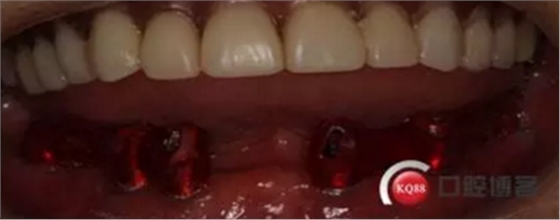

2)術(shù)前準(zhǔn)備及手術(shù)過(guò)程,測(cè)量血壓及血糖,簽種植知情同意書(shū);嚴(yán)格遵循無(wú)菌操作,局麻下采用微創(chuàng)技術(shù)于323436分別植入osstem4.0X10,4.0X10,4.5X7; 434446分別植入osstem4.0X1O,4.0X10,4.5X7.初期穩(wěn)定性均達(dá)到了35N.CM以上;嚴(yán)密縫合,止血,種植體位點(diǎn)和方向與設(shè)計(jì)一致。

3)在石膏模型上重寸舊義齒并且調(diào)整,即刻戴入患者口內(nèi),目的恢復(fù)患者一部分功能和減少軟組織腫脹